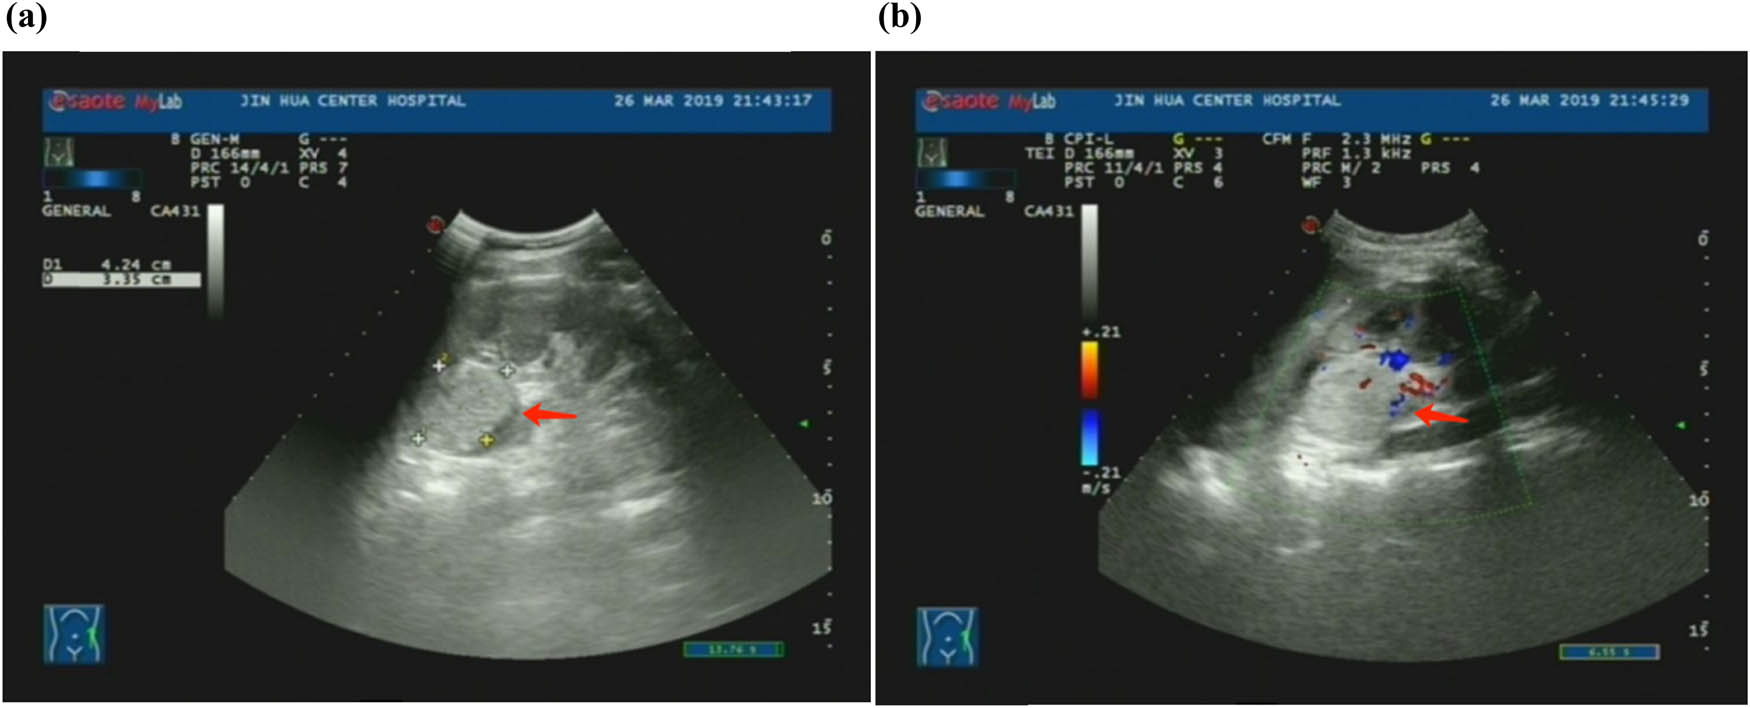

A 16-year-old female patient presented at the urology clinic on March 25, 2019, with a complaint of hematuria lasting for 5 days. The patient was admitted to the hospital to identify the cause of the hematuria. Enhanced computed tomography (eCT) showed the presence of a solid mass (3.2 cm × 3.1 cm) in the dorsal upper pole of the left kidney, with evidence of invasion into the upper renal calyces (Figure 1). These findings were confirmed by ultrasonography (Figure 2) and enhanced magnetic resonance imaging (MRI) (Figure 3). Despite the apparent indications for surgical intervention, the patient’s guardians opted for Chinese Traditional Medicine (TCM) as an alternative treatment for the tumor, refusing surgical intervention. The patient was discharged following comprehensive communication and the completion of a consent form declining surgery.

(a) Ultrasound showing a high echogenic area with internal uneven echo in the upper pole of the left kidney. (b) Ultrasound showing blood flow signal inside the echogenicity.